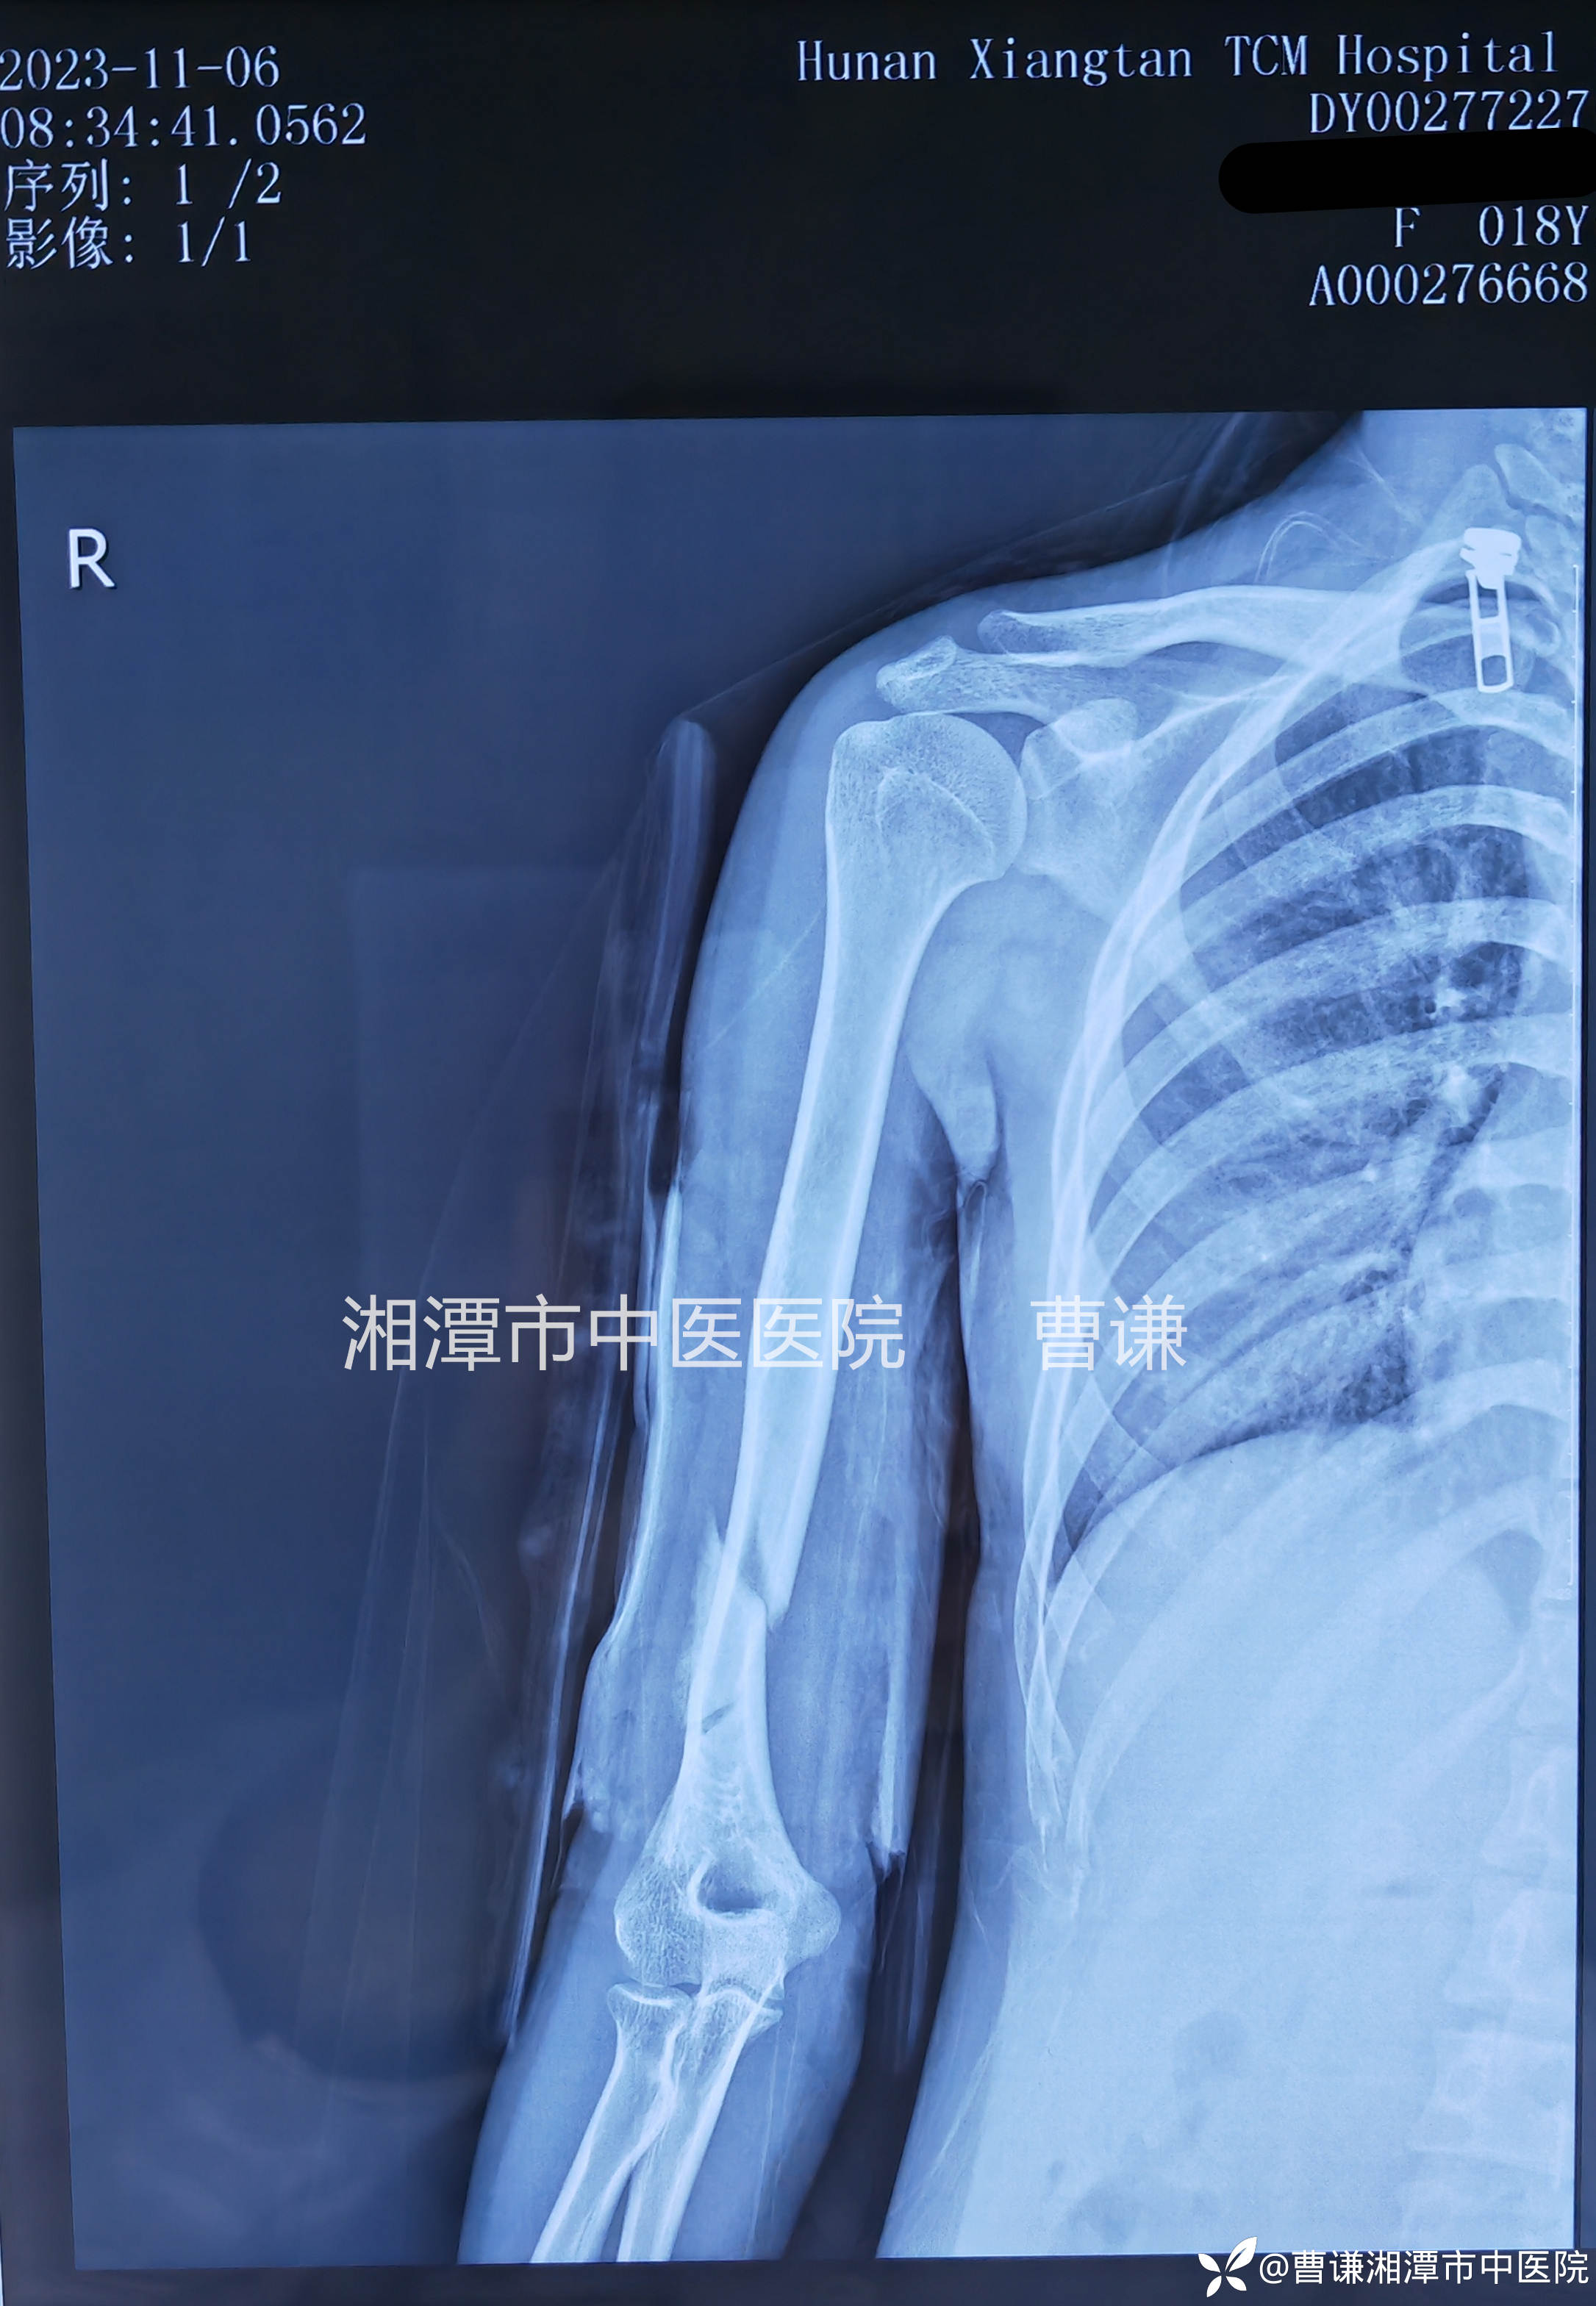

伤后一月余拍片复查骨折对位对线情况同前。

伤后一月体查患肢局部已无明显压痛及纵轴叩痛,患者已经可以主动上举患肢,但肘关节屈曲功能还受限,予以拆除直角托板,继续四块小夹板外固定,指导患者进行主动功能锻炼,患者回当地继续上课学习。